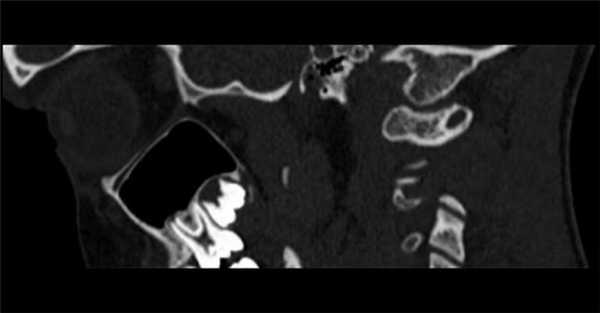

(Слева) На сагиттальной КТА визуализируется замкнутый костный мостик (аномалия Киммерле, полный вариант) над позвоночной артерией, расположенный вдоль верхнего края дуги С1.

3. КТ при аномалии Киммерле:

• КТ в костном окне:

о Полный или частичный костный мостик над отверстием позвоночной артерии в С1

• КТА:

о Позвоночная артерия в костном туннеле

о Мультипланарная КТ в костном окне с 3D реформатированием